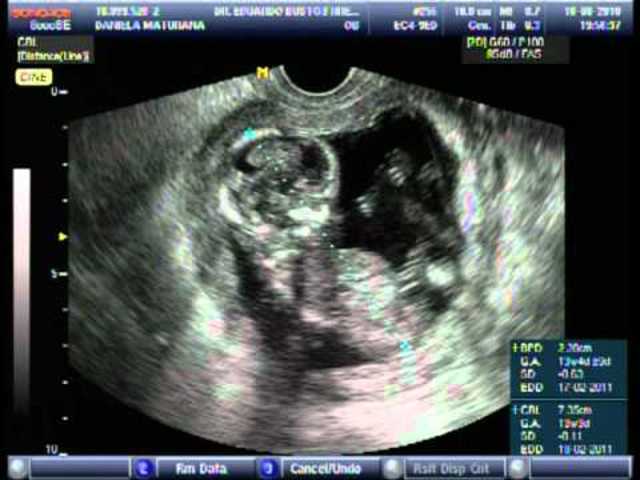

• Period: to

12-16 SDG

SDG 12-El fin del primer trimestre del embarazo. El interior de la boca está cubierto de papilas gustativas. Los movimientos intestinales comienzan. El material expelido del colon del feto y del recién nacido se llama meconio. Las extremidades superiores casi ha alcanzado su proporción final. Las extremidades inferiores aún no. La cara continúa madurando.

SDG 15, las células progenitoras sanguíneas llegan a la médula ósea y se multiplican. Primeros movimientos fetales.